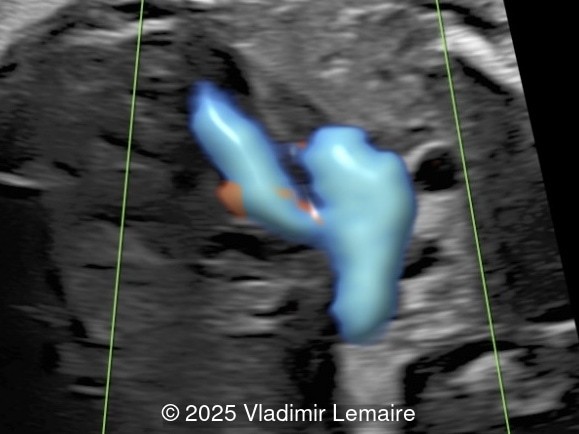

Our images demonstrate the following:

- Images 3 and 4: The five-chamber view shows the ventricular septal defect and the dilated overriding aorta.

- Image 5: The right ventricular outflow tract view with color Doppler demonstrates a small main pulmonary artery when compared to the dilated aorta due to pulmonary stenosis.

- Image 6: The three-vessel-trachea view with color Doppler shows the discrepant size of the great arteries with the pulmonary artery smaller than the aorta. Note the presence of antegrade blood flow in both arteries.

Color Doppler confirms the presence of an overriding aorta with blood draining from both ventricles, through the ventricular septal defect into the aortic root. Due to high perfusion, inflow into the aorta appears aliased. At the level of the three-vessel-trachea view, color Doppler can also demonstrate a small pulmonary artery. Flow is antegrade across the ductus arteriosus in mild Tetralogy of Fallot and can be reversed in severe cases. Color Doppler can help differentiate various subgroups of TOF as postnatal ductal dependency of the pulmonary circulation can be associated with cyanosis of the newborn.